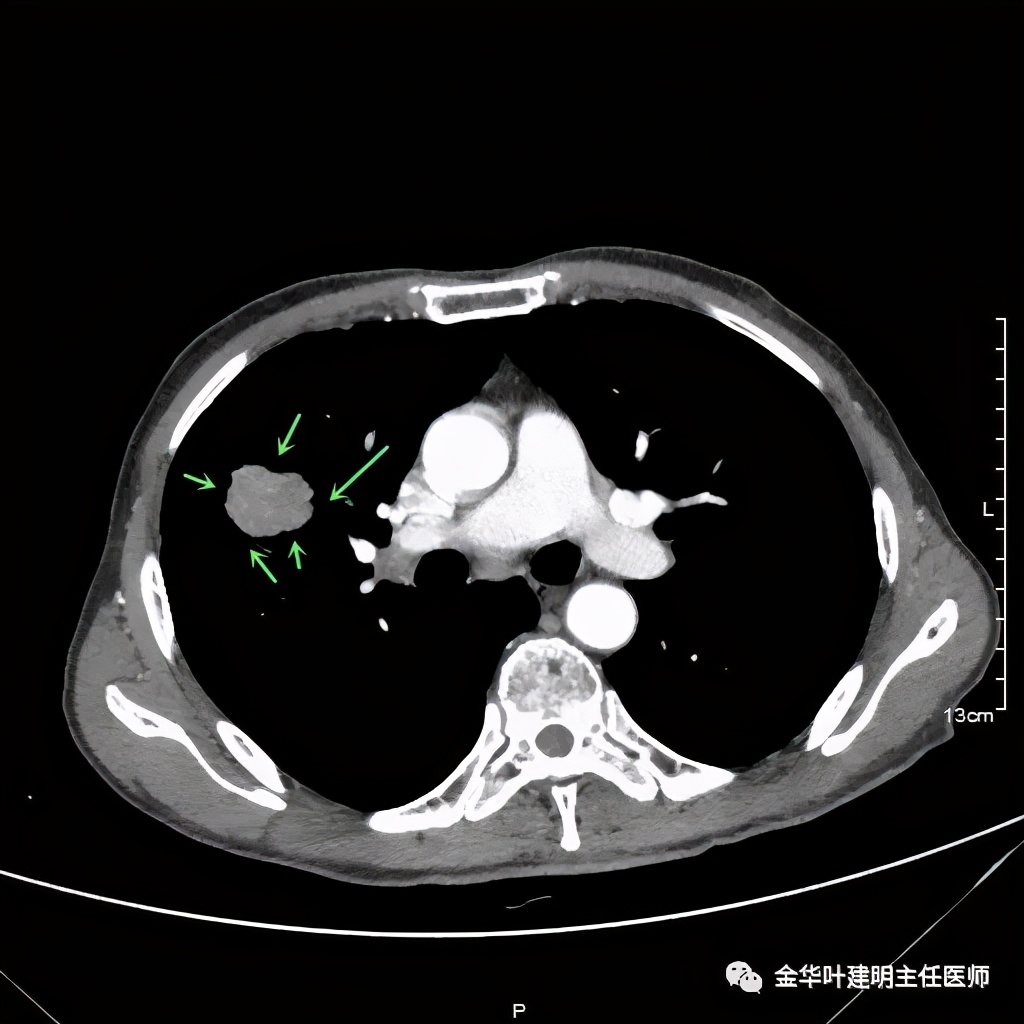

金华的某A,今年73岁,男性。检查发现右上肺占位,肿瘤筛查指标正常,血常规与CRP正常,临床有反复咳嗽、咳痰2年余(考虑慢支的关系,近期也许同时有病灶的影响)。一年前还在外院做过支气管镜,也未见确切异常。我们先来看他这次的胸部CT图像:

上图示病灶

上图示病灶边缘不太光整,内部密度不太均匀

上图紫色箭头示叶间胸膜受牵拉,病灶边缘部分见到细毛刺

上图示纵隔窗实性